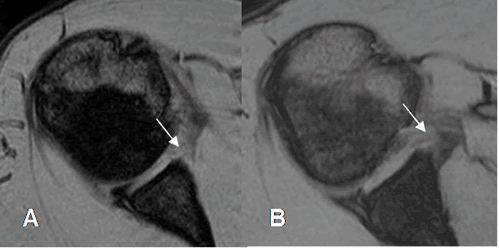

Fig 62. Lesión de Bankart.

A y B: RM axial en FFE. Alteración en la parte antero-inferior del labrum por lesión de Bankart.